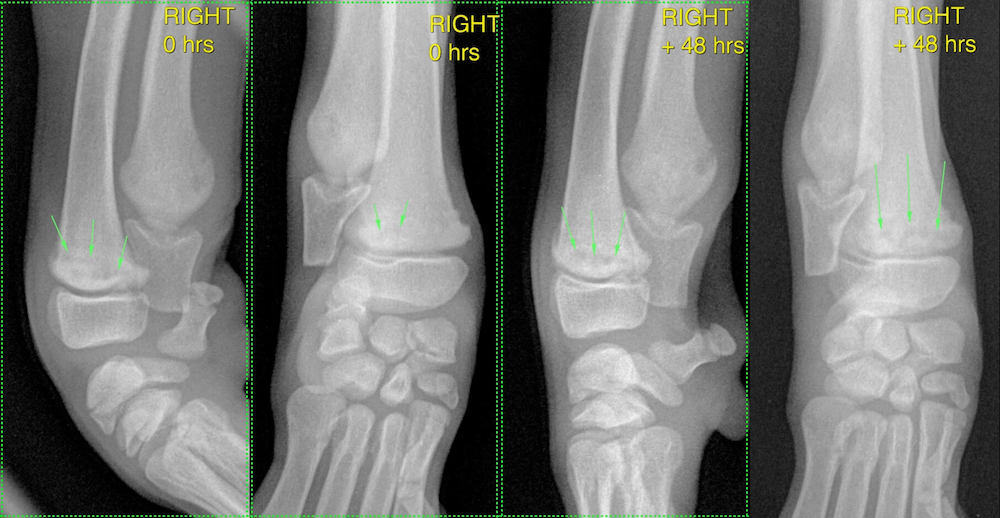

Mediolateral and dorsopalmar views of the right carpus at Zero hours (presentation) and +48 hours are shown:

Zero hours: on the mediolateral view irregular radiolucencies are visible in the radial metaphysis (green arrows). A subtle lucency is also evident in the caudal metaphysis of the ulna. On the dorsopalmar view, subtle radiolucencies in the radial metaphysis are highlighted (green arrows).

48 hours: on the mediolateral view radiolucencies in the radial metaphysis have coalesced to form a more linear lucency parallel to the physis. Also, note a more prominent lucency in the caudal metaphysis of the ulna. On the dorsopalmar view, multiple lucencies in the radial metaphysis are forming a somewhat linear pattern.